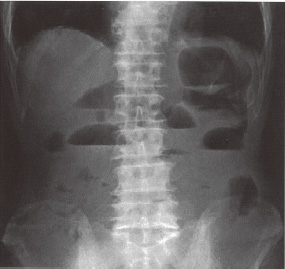

腸閉塞の病歴、理学所見そして腹部単純レン トゲン写真の見方はM5 の殆どが理解している ようだ。1 名だけ間違った回答をしているが、 この学生は無用な羞恥心を抱かずにすんだと思 われる。これを機会に基礎的な病態を学習すれば良い。

図4

図4 第1問(3)